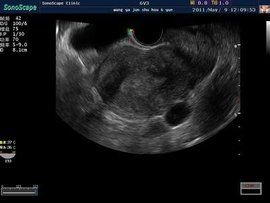

陰超,也就是陰道B超,又稱腔內B超,是將B超探頭放入 陰道或者 直腸進行 超聲診斷的方法,特別適合於觀察小 骨盆內的 盆腔臟器。與腹部B超相比,陰超的圖像更加清晰逼真、結果更準確,而且被檢者也不用“ 憋尿”。特別適合於 排卵監測、 宮外孕的確診、子宮占位性疾病以及 多囊卵巢綜合症和 朱古力囊腫的診斷。對於有過性生活的檢查者可以通過 陰道檢查,對於 處女可以通過直腸進行B超檢查。

月經周期子宮內膜一、正常月經周期子宮內膜聲像圖表現及正常卵巢內成熟與未成熟卵泡(所謂“測排卵”)。 二、子宮良性腫瘤:1、子宮腺肌病; 2、子宮肌瘤。 三、子宮惡性腫瘤:1、子宮內膜癌 ;2、子宮頸癌。 四、卵巢非贅生性囊腫:1、多囊腫卵巢綜合症; 2、朱古力囊腫。 五、卵巢腫瘤。 六、儘早明確診斷早期妊娠。 七、異常早期妊娠特別是異位妊娠(即“宮外孕”),由於宮外孕是臨床急症,搶救不及時亦 致死亡